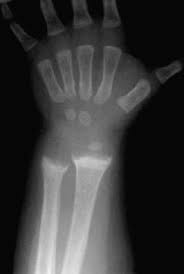

#vitamin_d Krivica alebo rachitída (rachitis) je ochorenie, ktoré sa prejavuje u detí. Je vyvolané nedostatkom vitamínu D, ale často býva spôsobená aj nedostatočnou výživou, najmä "chudobnou" na tento vitamín, ale aj nedostatkom slnečného žiarenia, pomocou ktorého dokáže telo vytvárať samé vitamín D.